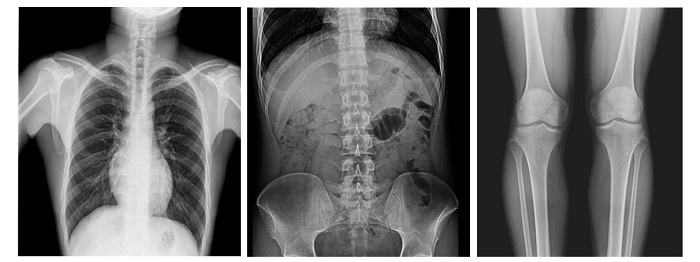

配備新一代動態平板探測器,17×17英寸大幅面成像,能對患者的胸部腹部等部位實現大范圍全覆蓋,透視檢查無需對患者重新定位便可觀察到足夠大的人體器官組織,避免漏診誤診;最高30幀/s采集幀速,影像更加流暢,便于使醫生觀察細微病變,從而提高診斷準確率。